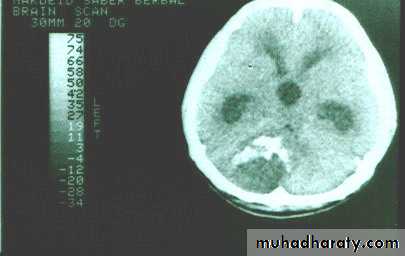

Posterior fosse tumor

Medullo blastoma

Age incidence between 5-15 Y represent about 35-40 %of PFT

Arise from the midline mainly within or from the roof of the 4 TH ventricle fill the fourth ventricle & seeding via the csf so can seen in the distal part of the spinal canal .

CT finding as well circumscribed lesion heterogeneous in density ,have solid & cystic part , with also scattered calcification little surrounded edema , the solid part is enhance

90 % present with obstructive hydrocephalous at the level of the 4Th V. with dilatation of the lateral V. ( body , frontal , temporal & third ventricle )